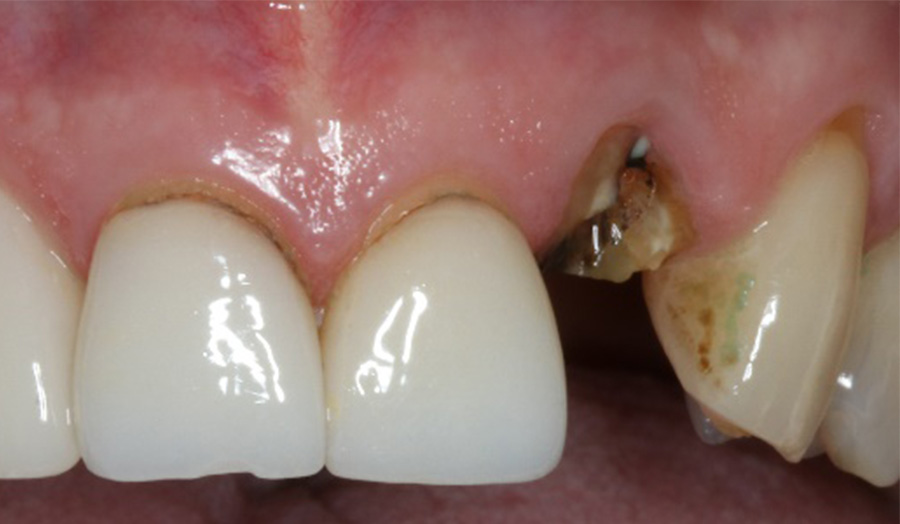

A 62-year-old male presented himself to my practice with a fractured non-restorable tooth #10. We planned a single implant with a surgical guide and a temporary bridge, both manufactured with Primeprint. The surgery was completed in 20 minutes, and it took us 10 minutes to bond the temporary bridge.

Before: Initial situation with a fractured non-restorable tooth #10